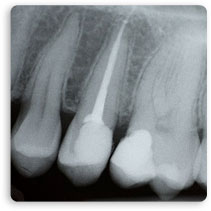

L'importanza di una cura canalare eseguita secondo determinati protocolli risulta importante per evitare eventuali problemi futuri al paziente. Il trattamento di un dente varia da 2 a più sedute, dipende dal numero di radici da trattare. Durante il trattamento di Devitalizzazione e a fine terapia vengono fatte sempre delle radiografie di controllo per valutare l'effettiva riuscita della cura.